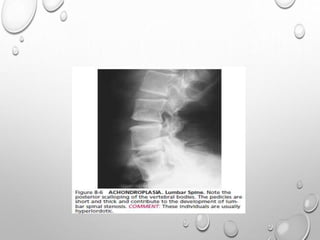

VERTEBRAE

LUMBOTHORACIC KYPHOSIS

LUMBER HYPER LORDOSIS

LENGTH GENERALLY NORMAL

PLATYSPONDYLY , DISC HEIGHT EQ TO VERTEBRAL BODY

POSTERIOR SCALLOPING

PEDICLES ARE SORT , THICK , INTERPEDICULAR DISTANCE DECREASED

ANGULAR KYPHOSIS AT THORACOLUMBER JUNCTION RESULTING FROM

ANTERIOR BEAKING OR BULLET NOSE VERTEBRAE

SPINAL CANAL STENOSIS ---- PATHOLOGIC HALLMARK